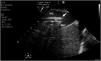

Vascular ultrasound allows us to measure vessel diameter to select the optimum cannula size (Fig. 1). The following formula is used for this purpose: cannula caliber (French (Fr)) = 3 × vessel diameter (mm). The largest cannula size should be used for both drainage and return, in order to ensure the greatest flow possible. Ultrasound-guided vascular puncture increases the safety and success rate at the first attempt, reducing the risk of local complications (arterial cannulation, cannulation of the saphenofemoral junction or transfixation of the inguinal ligament).20,11

During cannulation, using ultrasound, we can check the intravascular insertion of the guides and subsequently of the cannulas. In the case of using a double-lumen cannula, transesophageal echocardiography (TEE) is essential, since serious complications may occur during implantation (perforation of the RA or cava superior, migration towards the RV), and we must check the correct orientation of the return flow towards the tricuspid valve.21 In cannulation with a simple double cannula, we can use transthoracic echocardiography (TTE) or TEE in the absence of a good acoustic window. When using the femoral-jugular configuration, the draining cannula must be located in the inferior cava below the left suprahepatic vein, and the tip of the return cannula must be positioned at RA level (Fig. 2) (Supplementary material 3). In the femoral-femoral configuration, the draining cannula should be positioned in the inferior cava and the return cannula in the RA. The distance between the two cannulas should be at least 10 cm to avoid recirculation.